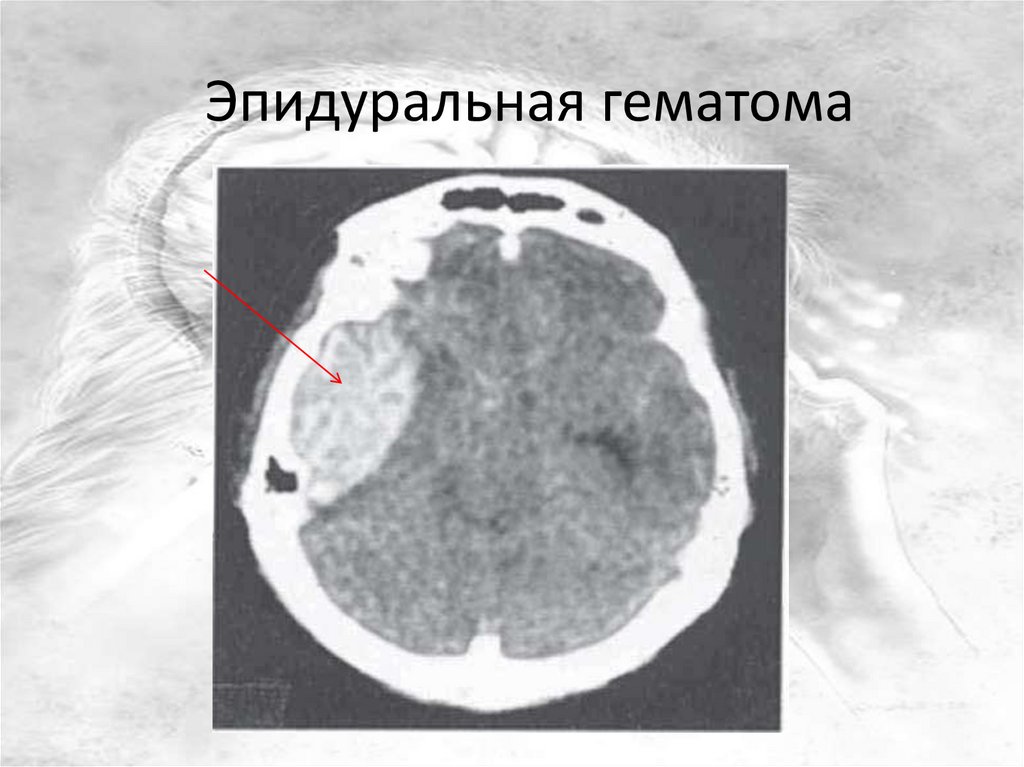

Эпидуральная гематома